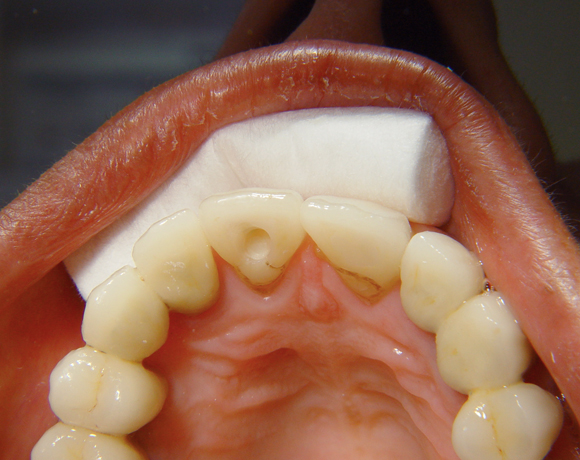

Bei diesem Patientenfall musste nach Neuüberkronung der Frontzähne eine Wurzelbehandlung erfolgen. Um der Gefahr aus dem Weg zu gehen, dass die neue Krone abbricht, da sehr wenig eigene Zahnrestsubstanz nach der endodontischen Behandlung übriggeblieben war, wurde der Zahn nachträglich mit einem Dentinpost versorgt.